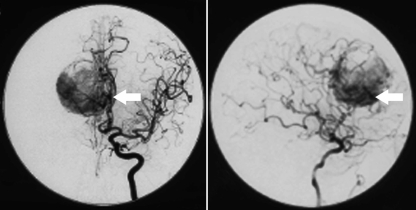

病人接受了術(shù)前血管造影。來(lái)自顳淺動(dòng)脈和腦膜中動(dòng)脈的頸外動(dòng)脈血供雙側(cè)栓塞。然而,更重要的供血來(lái)源于一條不能順利栓塞的大的右胼胝體邊緣動(dòng)脈。從該動(dòng)脈直接進(jìn)入腫瘤的大反差射流表明,在任何腫瘤縮小之前,需要成功地處理該供血血管(圖2)。

圖2:術(shù)前血管造影。術(shù)前前后和側(cè)位腦血管造影顯示大的胼胝體邊緣動(dòng)脈,動(dòng)脈射流進(jìn)入腫瘤(箭頭)